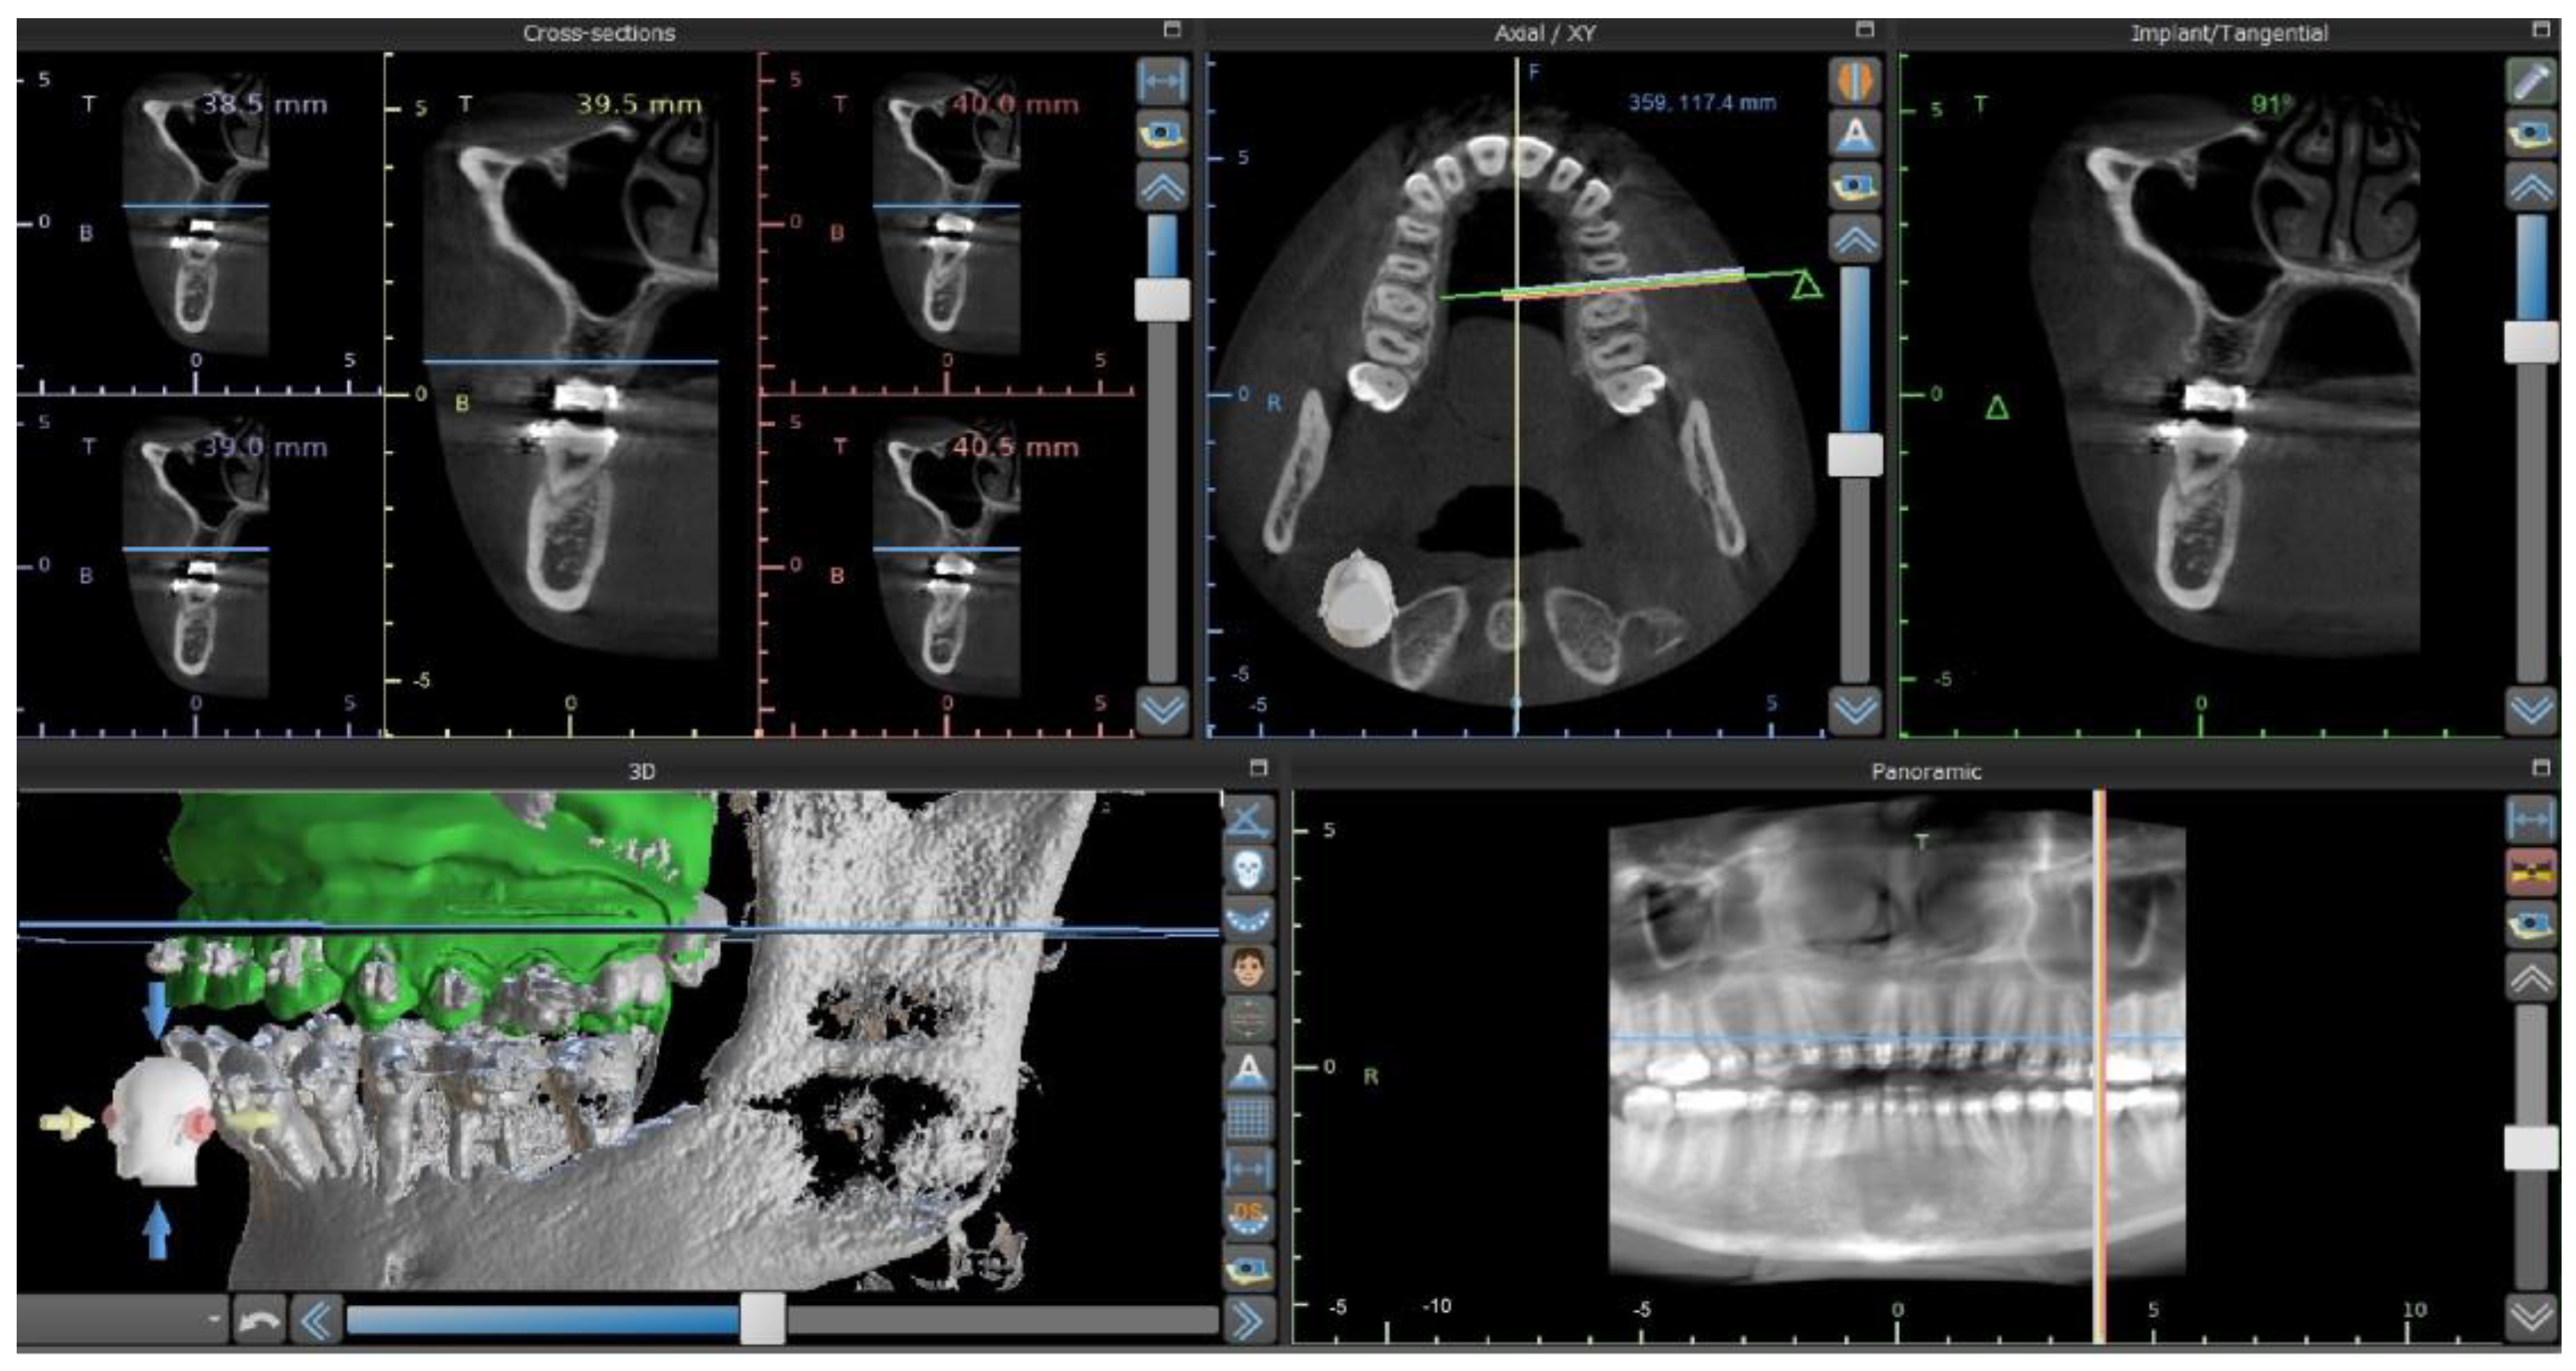

2. Materials and Methods